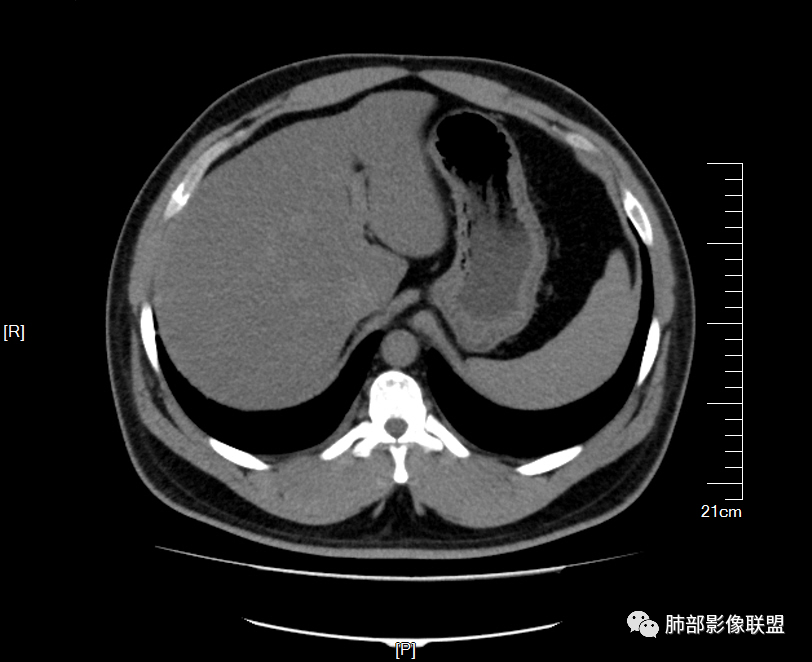

男32岁。既往曾发现血肌酐升高.此次因左足痛6天入院。有痛风、高血压病史。两肺弥漫性的病变,小片状或者结节状为主病变,小叶中心分部为主,边界不清。心影比较饱满,肝实质密度均匀的降低。考虑为肝损害的影像学改变。综合考虑多功能脏器的损害,肺部损害肺泡炎?肺水肿?或病毒性的肺炎?

少量积液,脂肪肝

转移性钙化继发于甲旁亢和慢性肾衰

磷酸钙沉积在肺泡间隔

继发甲状旁腺机能亢进?骨钙?

甲旁亢,肾功能不全,都可以发生